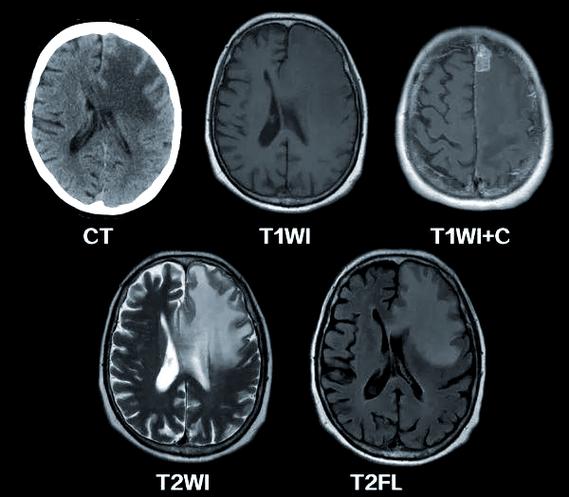

首先要肯定,MRI,尤其是弥散加权成像(DWI)序列,对于诊断急性期(数小时内)脑梗死是极其敏感和准确的。

- 原理:脑梗死后,脑细胞缺血缺氧,细胞内的水分会从细胞内转移到细胞外,导致水分子的“布朗运动”受限,DWI序列对这种水分子的微观运动非常敏感,一旦受限,病灶就会在DWI图像上显示出高信号(亮斑),而在表观弥散系数图上显示为低信号,这种“不匹配”现象在发病后几分钟到几小时内就会出现,比传统的CT和常规MRI要早得多。

- 时间窗:对于典型的急性脑梗死,如果DWI显示正常,那么在绝大多数情况下,可以认为没有发生新的大面积或典型的脑梗死,这是目前临床上最可靠的早期排除脑梗死的影像学方法。